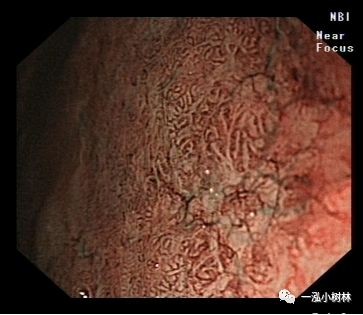

NBI+ME内镜表现:萎缩区域NBI放大可见胃小凹消失或不清晰,树枝状血管显露,黏膜苍白及萎缩边界更明显,多以幽门胃窦部为中心,随着萎缩的加重,胃体黏膜也散见,肠化区域可见胃小凹呈绒毛状,可见到“亮蓝嵴”“白色不透明物质”征。

例2

女性,60岁,慢性萎缩性胃炎伴肠上皮化生,Hp+

亮蓝嵴(LBC):位于上皮细胞表面呈脑回样结构脊部的纤细、蓝白色的腺样结构。特征:NBI才能观察到。NBI显示亮蓝色细线样反光,位于上皮细胞边缘。提示肠上皮化生刷状缘。是内镜诊断胃黏膜肠上皮化生的有效标志。